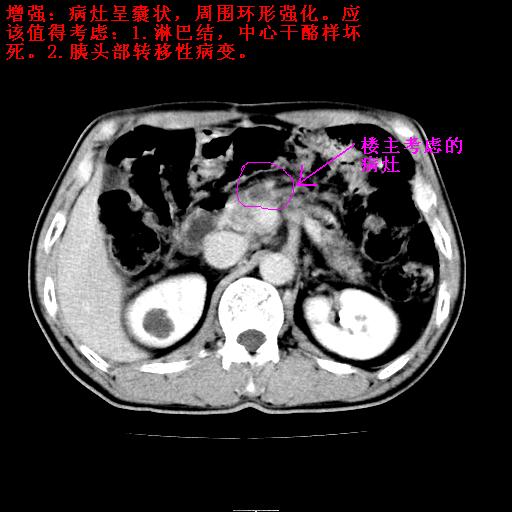

病灶确实存在,请看以下2幅图片:

另外,胰腺体部密度在平扫和增强时均不太均匀,似有数个小的囊状低密度区存在。不知道增强时其他期如何?应该高度警惕为转移性病变。

胰头右侧低密度影卡考虑为肠管;胰头前部低密度影,增强环形强化,结合临床首先考虑转移灶,其次考虑淋巴结结核(中心干酪性坏死)。

如是转移灶强化多为均质强化。如是结核应见到完整的壁且壁略厚。如是转移虽壁可不完整但内壁应该不规则。所以不支持是结核或转移。敬请指正!